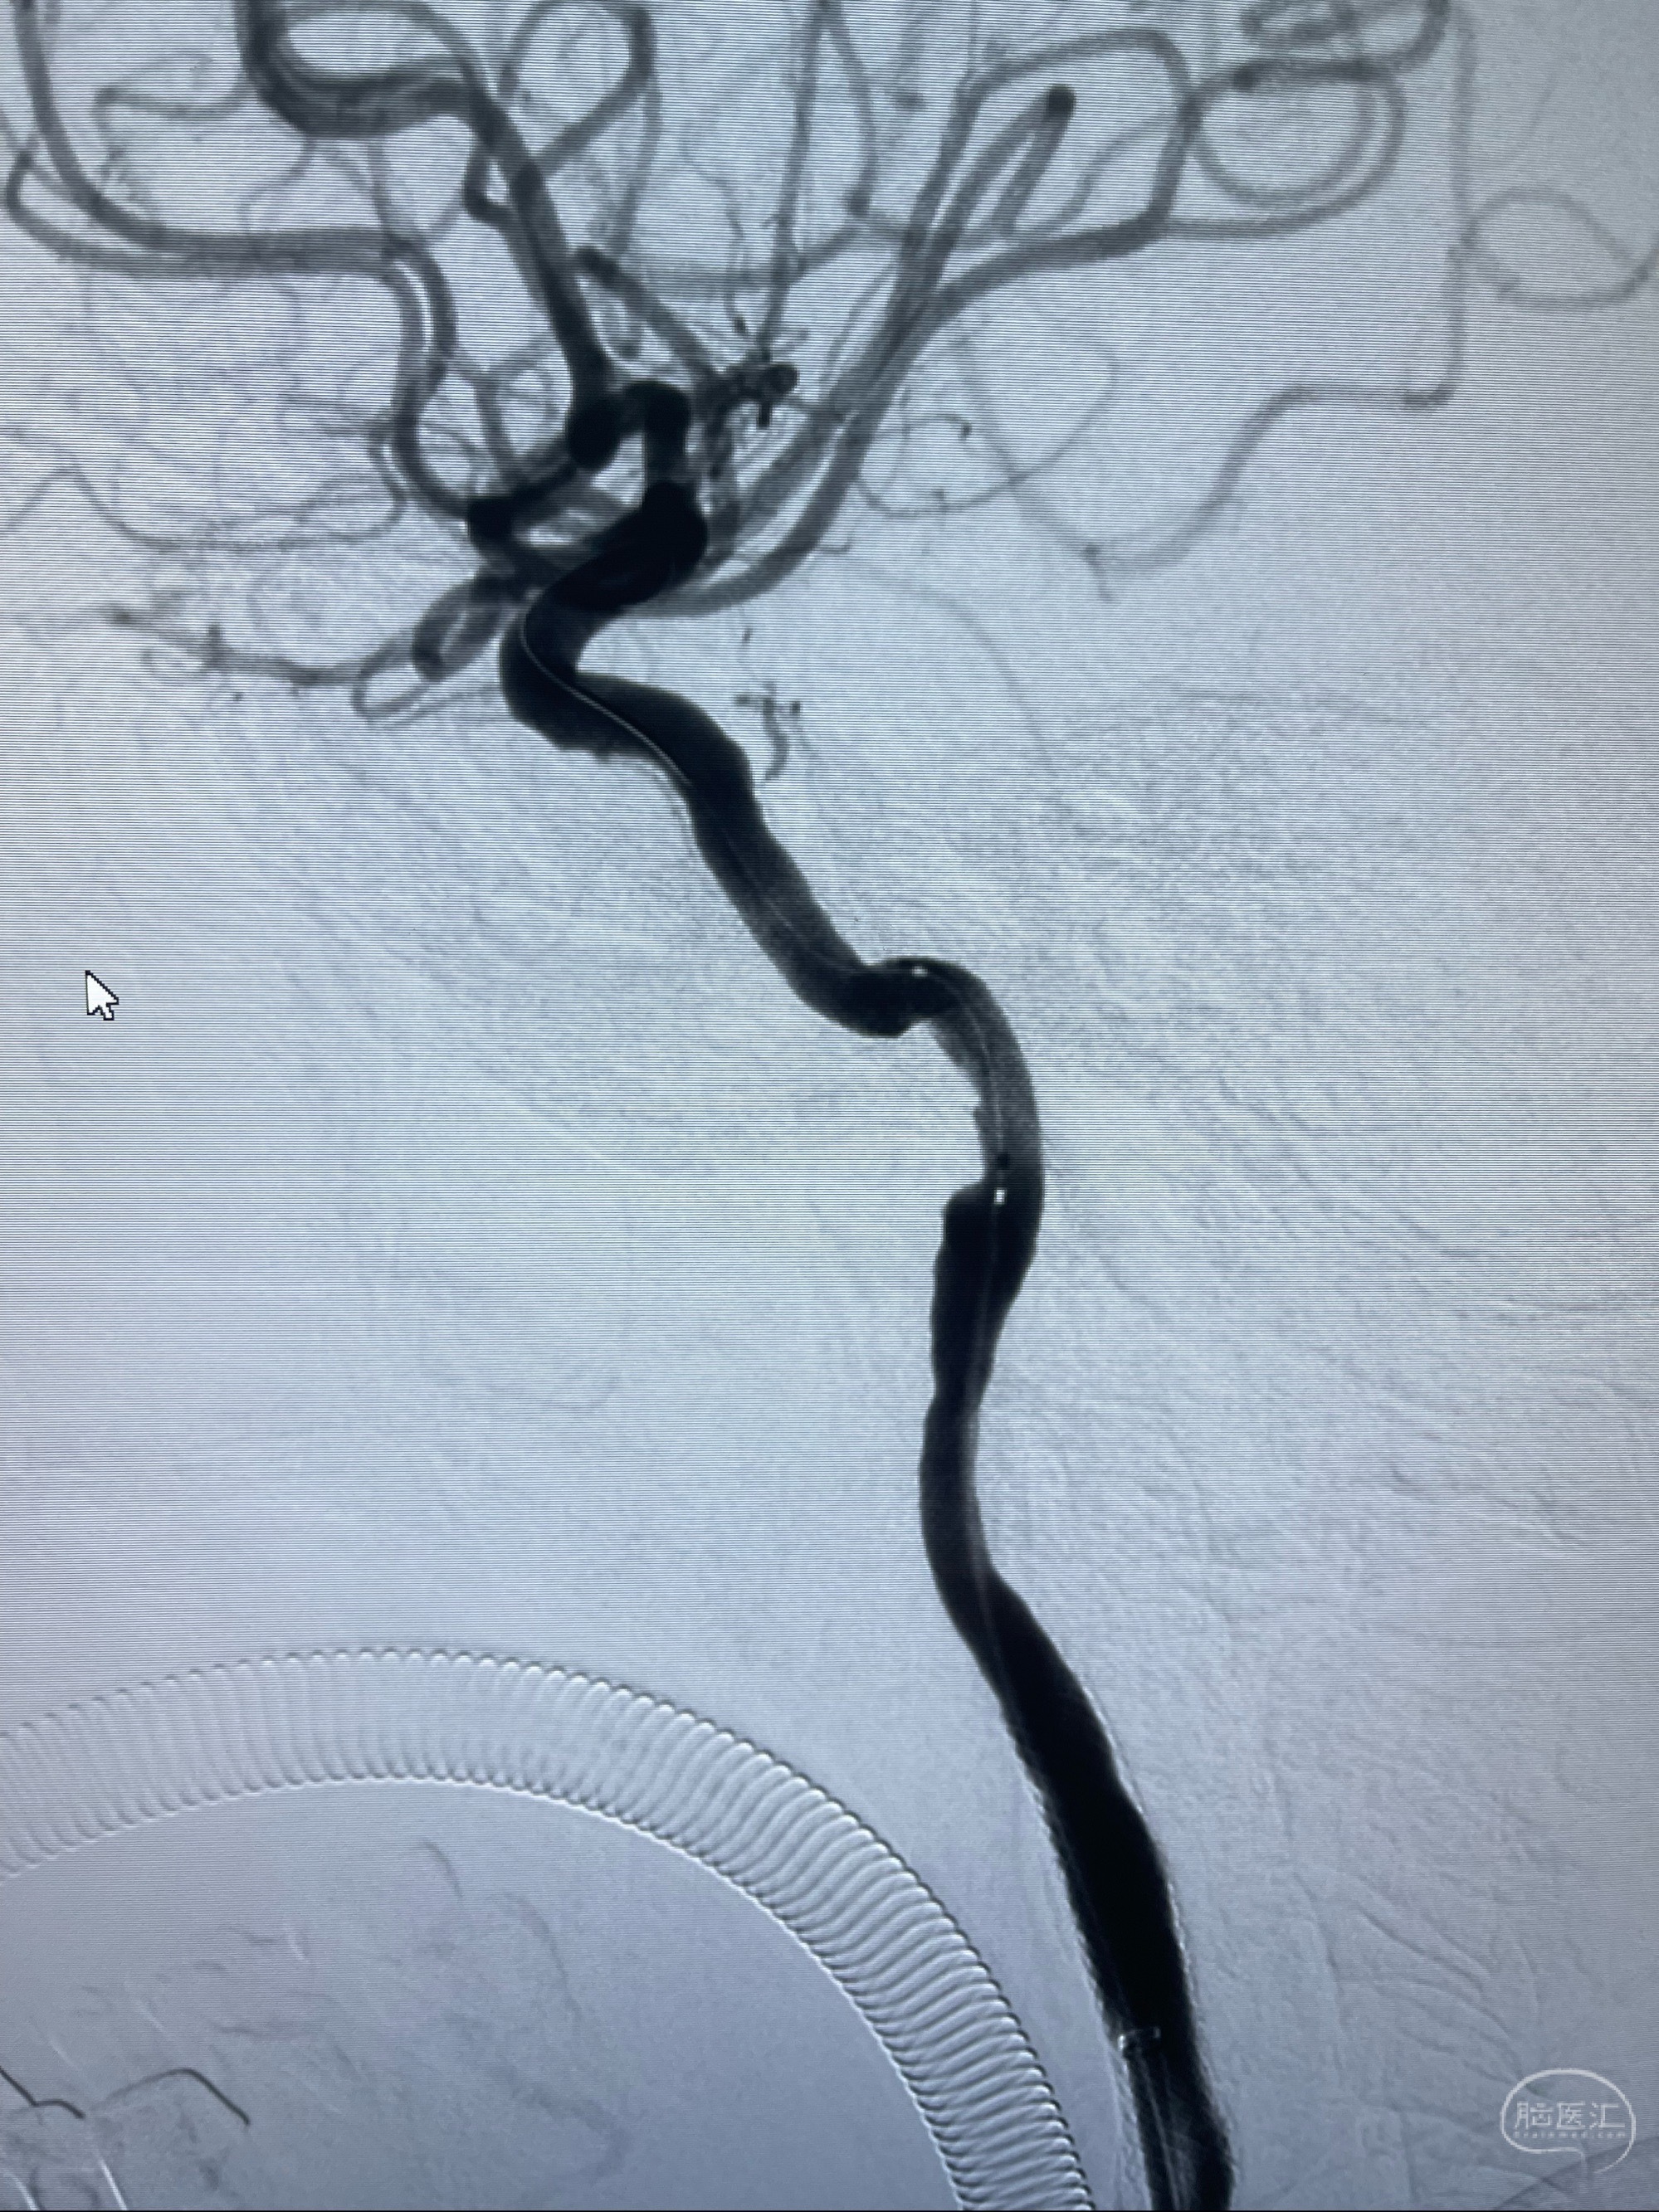

路径图下,5.5-50mmLeo支架导管在微导丝引导下超选择性插入远段Leo支架内

两枚支架部分重叠

多次确认支架位置及打开贴壁情况

支架完全打开,近心端位于原颈动脉支架远心端内

麻醉苏醒佳,遵嘱活动!

术后给予替罗非班300ug/h维持,序贯阿司匹林100mg➕泰嘉75mg口服